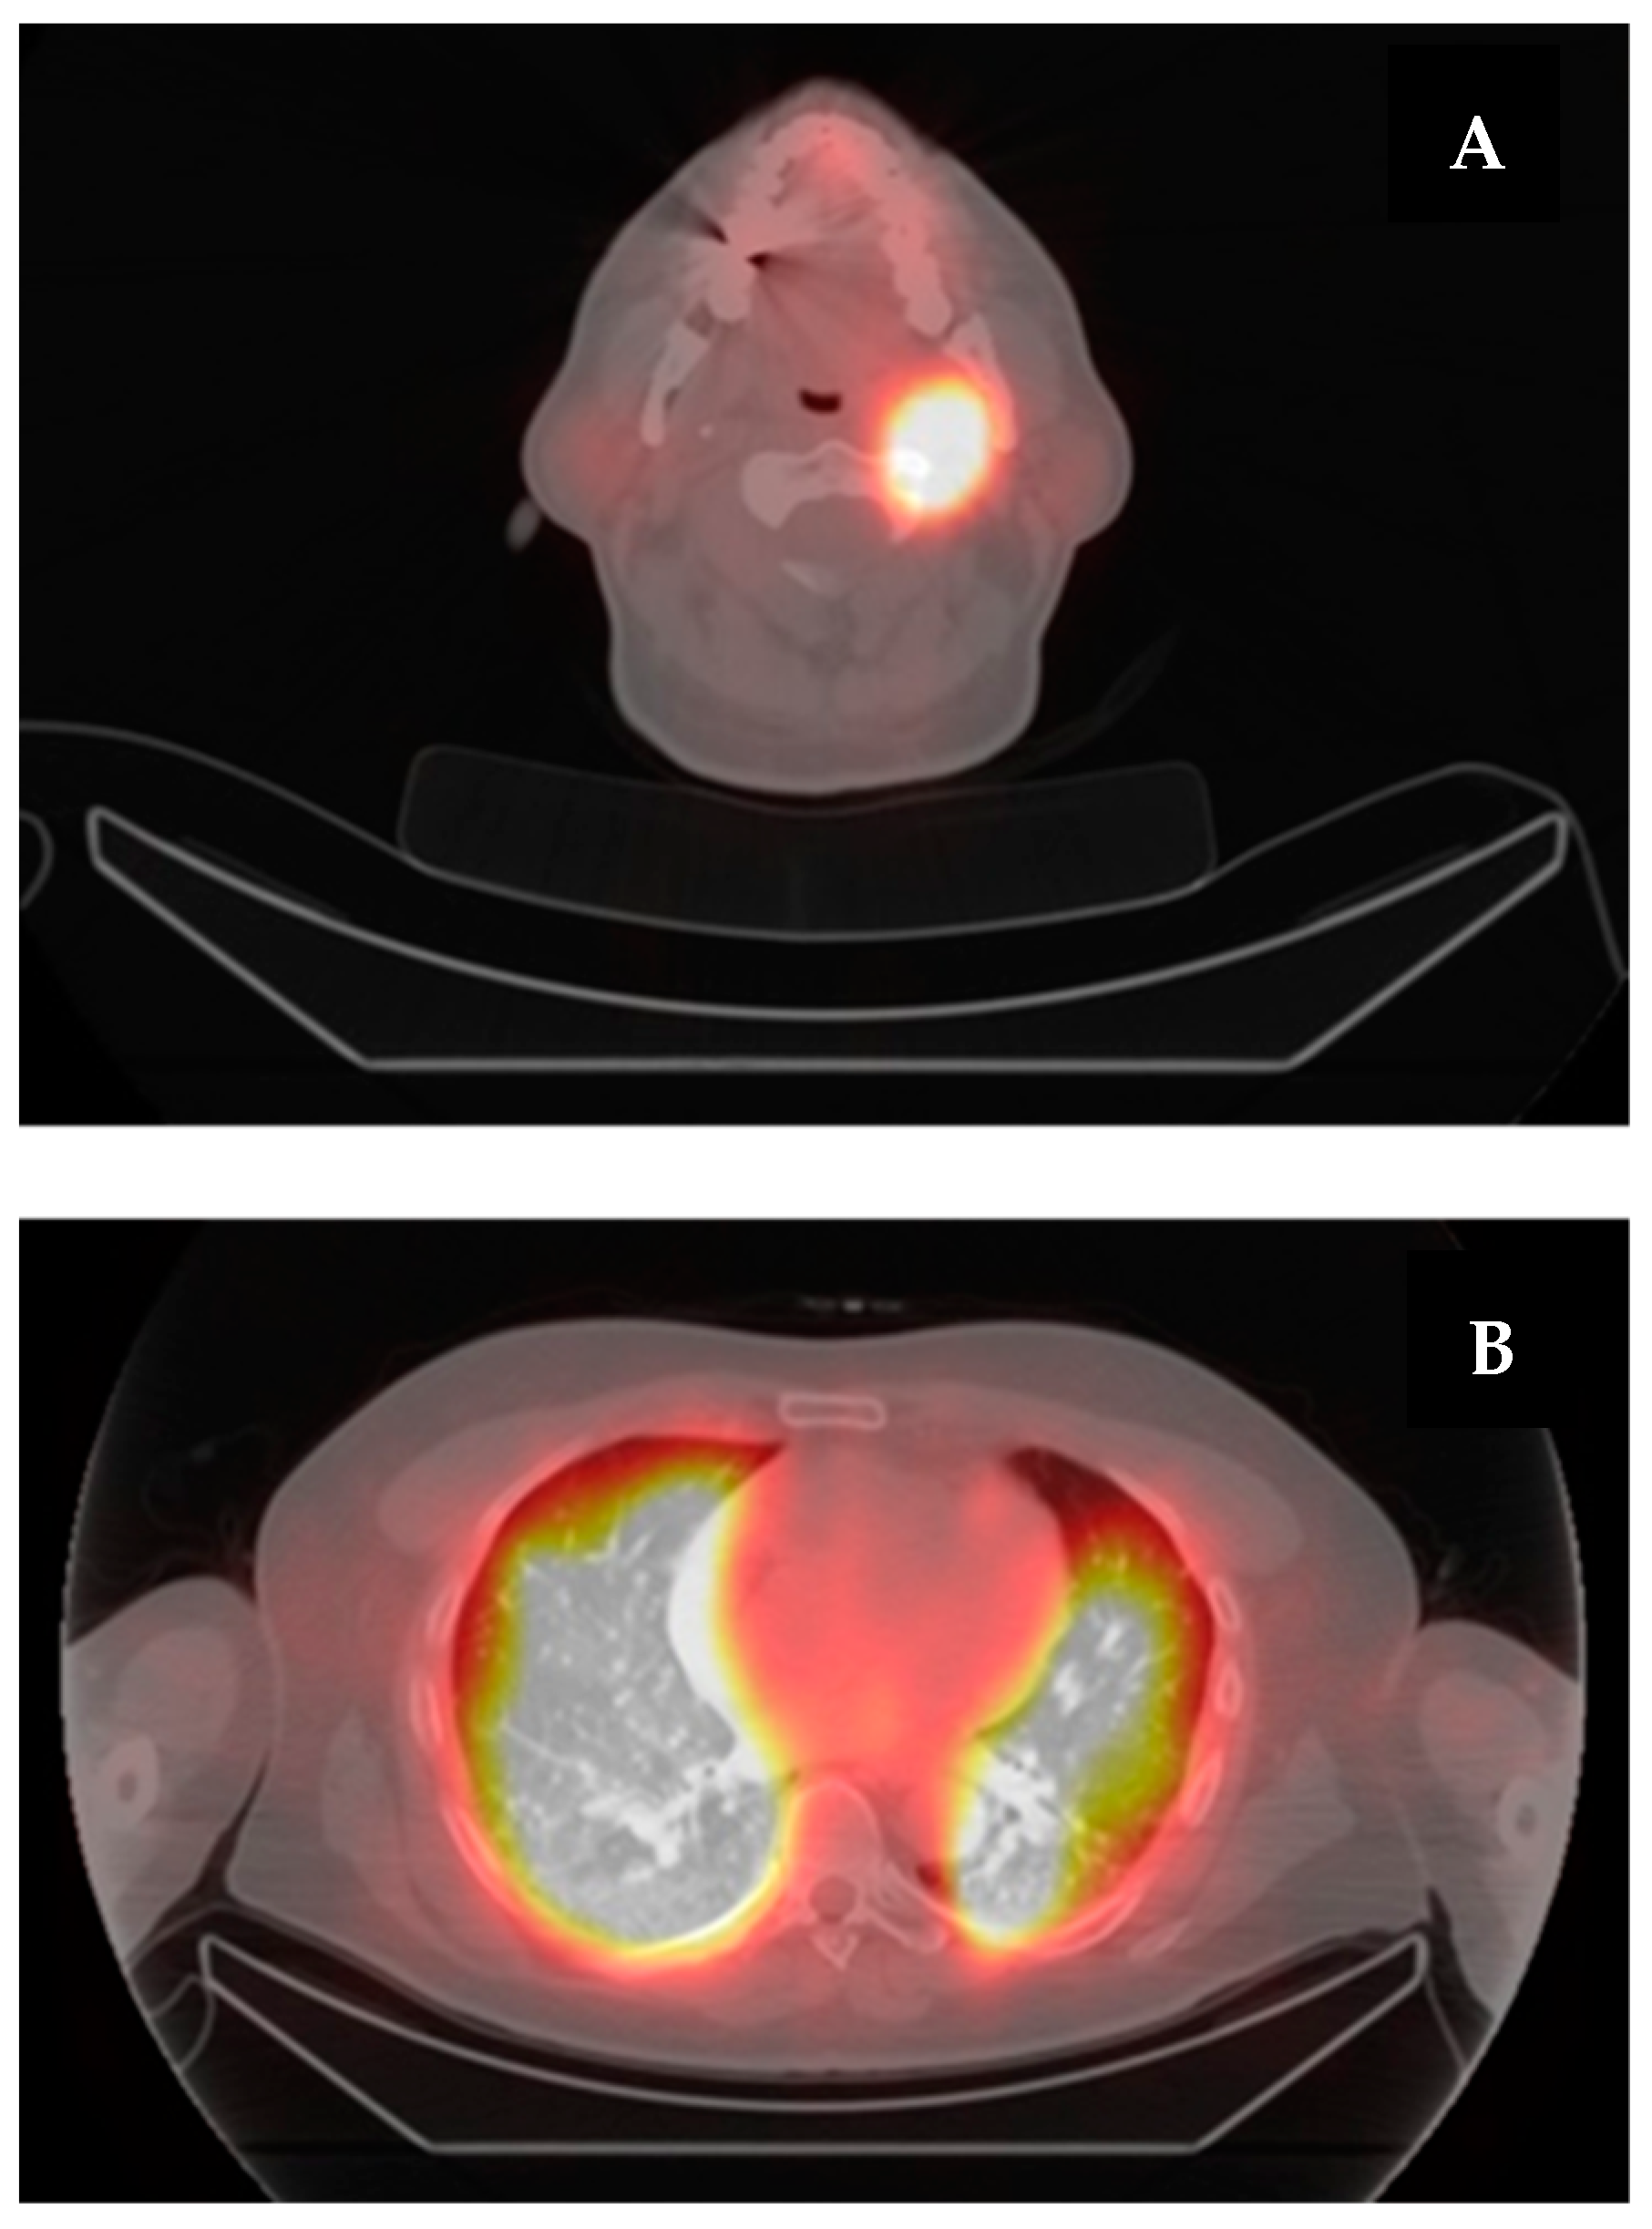

6. A Case of Re-Differentiation

|